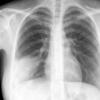

Case 3 RM & UL pneum PA

Date: 07/04/2004

Views: 5881